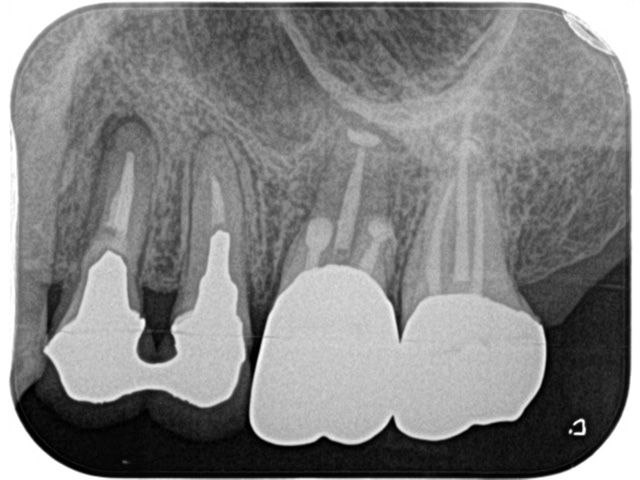

Before

After

| 主訴 | 右上の奥歯が咬むと痛む |

| 治療内容 | 右上第一大臼歯、第二大臼歯の精密根管治療 |

| 治療回数・期間 | 3回(3週間) |

| 費用 | 保険適応 |

| リスク・副作用 | 根管治療は術前の精密な診査診断および無菌環境下での治療によって成功率は高まってきましたが治療の成否を決める多くの要素があるため、根管治療がなされた後も再治療や外科処置、抜歯となる可能性が少なからずあります。また治療中には器具の破折や穿孔、修復物の損傷、歯の破折、術中・術後の痛みや腫れが生じることが稀にあります。根尖病変(再感染)を防ぐには適合の良好な補綴物を作製することや定期的なかみ合わせのチェックが必要です。 |